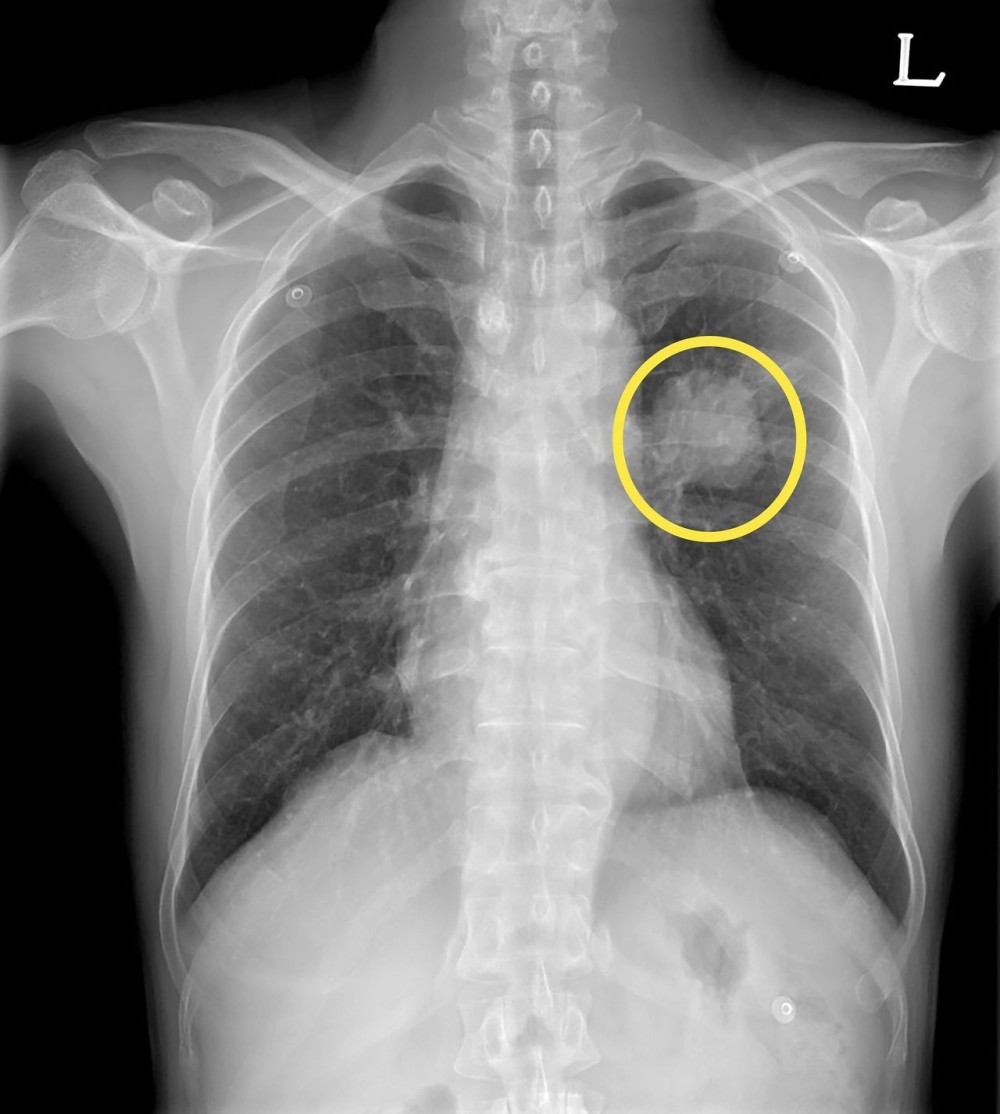

폐암 환자의 엑스레이 검사 사진

폐암 환자의 CT 검사 사진